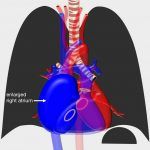

Hình ảnh bất thường bóng tim trên phim X-quang ngực.